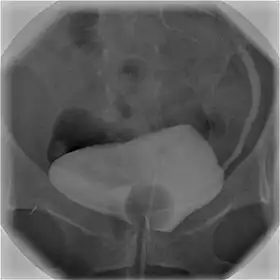

![]() Cystography image showing contrast in the urinary bladder and left ureter (right side of image). | |

Using a urinary catheter, radiocontrast is instilled in the bladder, and X-ray imaging is performed. Cystography can be used to evaluate bladder cancer, vesicoureteral reflux, bladder polyps, and hydronephrosis. It requires less radiation than pelvic CT, although it is less sensitive and specific than MRI or CT. In adult cases, the patient is typically instructed to void three times, after which a post voiding image is obtained to see how much urine is left within the bladder (residual urine), which is useful to evaluate bladder contraction dysfunction. A final radiograph of the kidneys after the procedure is finished is performed to evaluate for occult vesicoureteral reflux that was not seen during the procedure itself.[1]